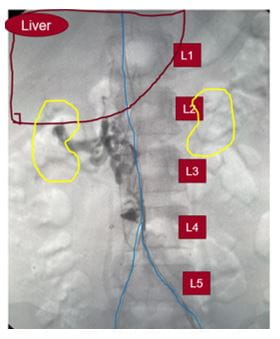

Congenital anomaly before interventionCongenital anomaly before intervention

Her overall clinical history, presentation and imaging was consistent with the patient having a congenital occlusion of the retro-hepatic inferior vena cava, the portion of the major vessel lying behind the liver.

“There are different anatomic variants of congenital IVC anomalies, primarily from an abnormal regression or persistence of the embryologic veins,” she adds. “Although most anomalies are asymptomatic, they can cause lower extremity venous insufficiency, deep vein thrombosis, pelvic congestion syndrome and can affect the planning of vascular procedures, so they’re really important to identify. With our case, this particular anatomy has a prevalence of less than 0.6 percent.”

To address the problem, Dr. Harth performed a staged complete IVC and bilateral iliofemoral thrombectomy and recanalization. In addition, she reconstructed the patient’s congenitally occluded retro-hepatic IVC with IVC stenting.

“Repeat mechanical thrombectomy with a larger device of the residual thrombus allowed us to remove more of the chronic, sub-acute thrombus that we couldn’t remove with suction thrombectomy,” Dr. Harth says. “We then proceeded to dilate up her retro-hepatic IVC which originally started off as an occluded vessel, to a 20 mm diameter with intravascular ultrasound and venographic guidance and ultimately deployed a 20 mm stent.”